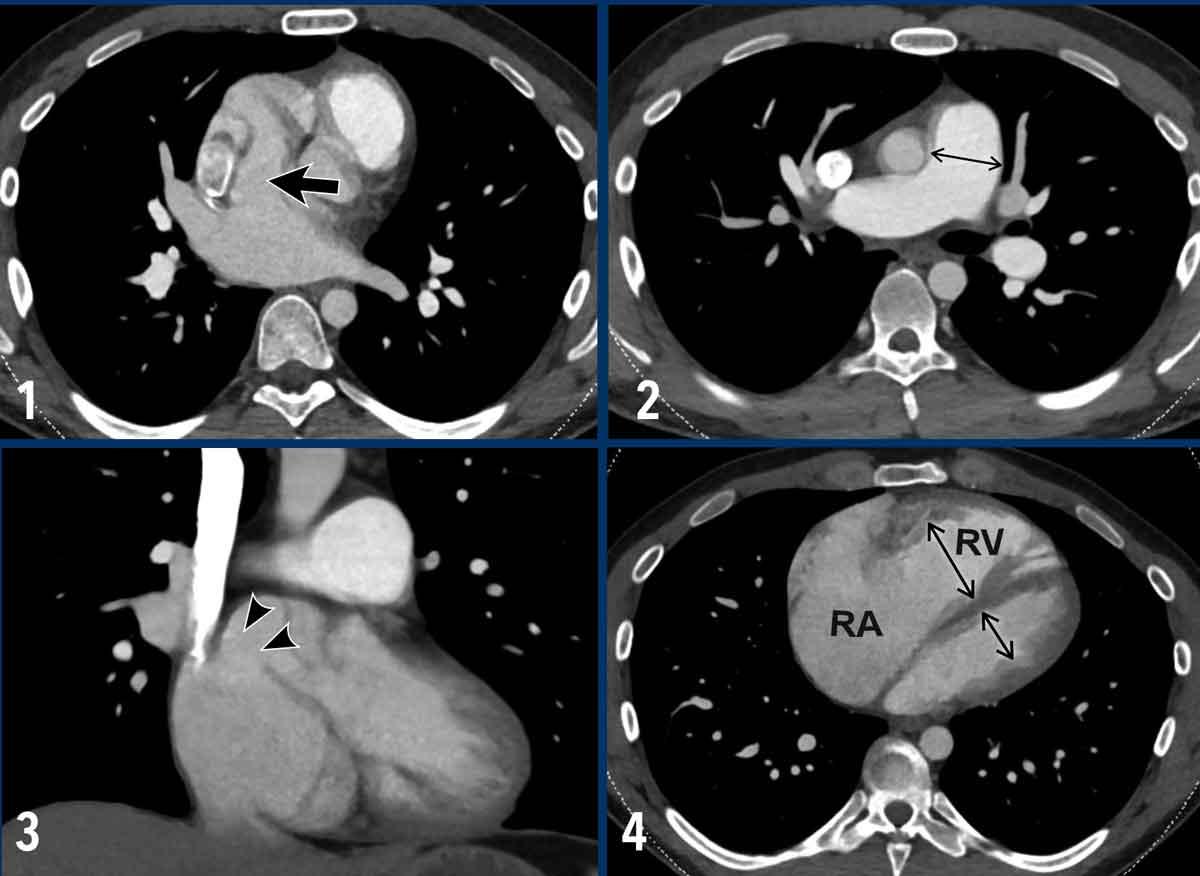

Giãn Thất Phải

Các hình ảnh cho thấy thất phải và thất trái bình thường so với thất phải bị giãn.

Các giá trị ngưỡng được đề xuất để đánh giá giãn tim phải trên CT lát cắt ngang:

- Nhĩ phải: ≥ 65mm (nữ) và ≥ 70mm (nam)

- Thất phải: ≥ 55mm (nữ) và ≥ 60mm (nam)

Trên mặt cắt trục ngắn, thất trái bình thường có hình dạng tròn đến bầu dục.

Vách liên thất góp phần tạo nên đường viền tròn của thành tâm thất.

Vách liên thất bị dẹt hoặc vồng sang trái là dấu hiệu chỉ điểm quá tải áp lực và giãn thất phải.

Tái cấu trúc tim trong thuyên tắc phổi

Đánh giá tình trạng tái cấu trúc thất phải có thể giúp phân biệt thuyên tắc cấp tính và mạn tính.

Dưới đây là hai ví dụ về bệnh nhân thuyên tắc phổi có tái cấu trúc tim.

Hình ảnh

- Có giãn thất phải với vách liên thất bị dẹt, nhưng không có bằng chứng phì đại thành thất phải (mũi tên đen), phù hợp với tình trạng tăng hậu tải thất phải cấp tính.

Hình ảnh này có thể gặp ở bệnh nhân thuyên tắc phổi cấp tính. - Ngược lại, ở bệnh nhân này có giãn thất phải và nhĩ phải kèm vách liên thất bị dẹt, đi kèm với dày thành thất phải (mũi tên trắng).

Điều này gợi ý tình trạng quá tải áp lực mạn tính và là dấu hiệu của tăng áp động mạch phổi lâu dài.

Hình ảnh này có thể gặp ở bệnh nhân tăng áp động mạch phổi do huyết khối tắc mạch mạn tính.